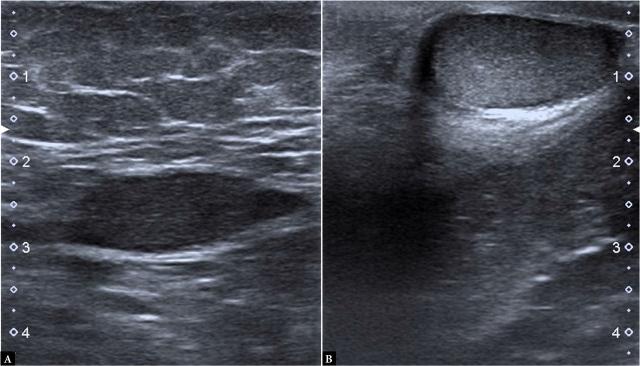

Ultrasound elastography is a simple non-invasive method for measuring tissue elasticity in relation to tissue fibrosis. The aim of this study was to compare echogenicity, volume and shear wave velocities of undescended vs normally descended testes.

Sixty-six boys with undescended testes were included in this study. The median age range was 35.5 (10-118) months old. The cases included in this prospective study consisted of 66 patients with non-operated undescended testes, with 51 of them being affected unilaterally and 15 affected bilaterally, as diagnosed by physical examination. The control group consisted of 31 healthy boys without any particular health problems. This prospective study was performed by gray-scale ultrasonography and shear wave elastography in boys with undescended testes and healthy testes. The testicular volumes were established by ultrasound measurement, the echogenicity and shear wave elastography values were measured in boys with unilateral and bilateral undescended testes, and the results were compared with healthy boys' testes and their contralateral testes. The stiffness values were recorded for speed (m/s) and elasticity (kPa), and the stiffness values of undescended testes were compared with the healthy control group.

Echogenicity values were lower in the bilateral undescended testes group than in the healthy group, and the healthy group's echogenicity was normal ( <0.001). The ROC curve was used to identify a cut-off shear wave elastography value for predicting decreased testicular echogenicity by using average shear wave elastography values. The area under the curve for the undescended testes was 0.78 (95% CI: 0.70-0.85, sensitivity 83.7%, specificity 68.7%, <0.001), with an average shear wave elastography value of 2.32 (m/s) for above the cut-off point indicates. This was found to be significantly associated with reduced echogenicity on gray-scale ultrasonography, suggesting that it may be correlated with fibrosis developing in patients with undescended testes.

The study provides interesting findings in that it proposes an alternative non-invasive method for the assessment of testicular tissue in undescended testes. We used shear wave elastography to compare the stiffness of normal testes in both heathy patients and in the contralateral healthy testes of boys with undescended testes, with the values obtained for the undescended testes reflecting the level of fibrosis of the parenchyma. Another outcome of this study was observed in patients with unilateral undescended testes, where the normally descended testes showed increased shear wave elastography values, which could be an early indication of parenchymal change.